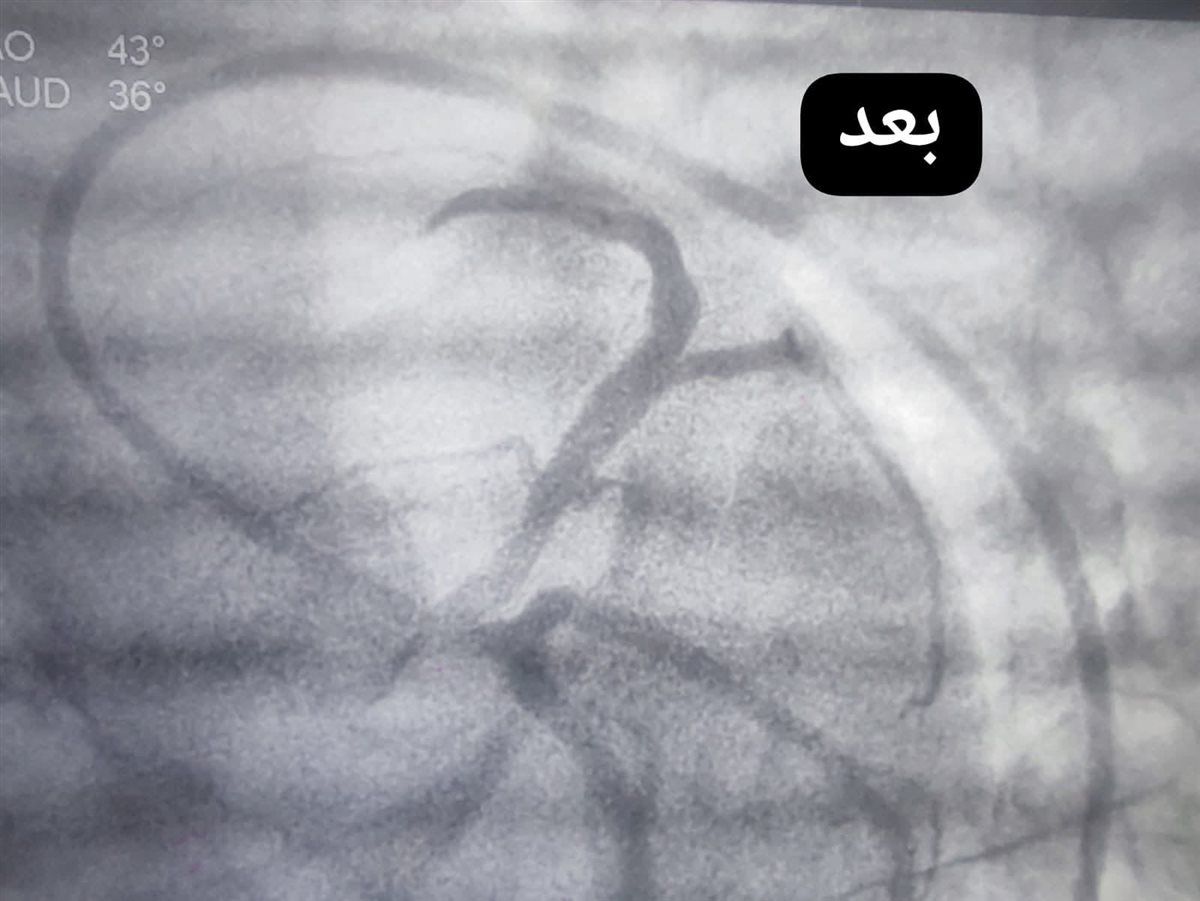

نجح الفريق الطبي بوحدة القسطرة القلبية بمستشفى قنا العام، فحالةى التعامل مع حالة حرجة لفتاة في مقتبل العمر، حيث أظهرت الفحوصات ورسم القلب إصابتها بجلطة حادة مع انسداد كامل في الشريان التاجي الأمامي الرئيسي، وهو ما استدعى التدخل الفوري لإنقاذ حياتها.

وعلى الفور، باشر فريق الإنعاش التعامل مع الحالة، وتمكن من إعادة النبض بنجاح، لتُجرى بعدها قسطرة قلبية علاجية عاجلة، أسفرت عن فتح الانسداد في الشريان التاجي الأمامي الرئيسي بنجاح تام.

وأسفر التدخل السريع عن تحسن ملحوظ في وظائف القلب، واستقرار الحالة الصحية للمريضة، التي غادرت المستشفى بعد أيام قليلة في حالة جيدة.